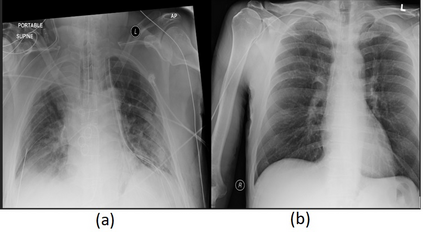

Deep learning (DL) analysis of Chest X-ray (CXR) and Computed tomography (CT) images has garnered a lot of attention in recent times due to the COVID-19 pandemic. Convolutional Neural Networks (CNNs) are well suited for the image analysis tasks when trained on humongous amounts of data. Applications developed for medical image analysis require high sensitivity and precision compared to any other fields. Most of the tools proposed for detection of COVID-19 claims to have high sensitivity and recalls but have failed to generalize and perform when tested on unseen datasets. This encouraged us to develop a CNN model, analyze and understand the performance of it by visualizing the predictions of the model using class activation maps generated using (Gradient-weighted Class Activation Mapping) Grad-CAM technique. This study provides a detailed discussion of the success and failure of the proposed model at an image level. Performance of the model is compared with state-of-the-art DL models and shown to be comparable. The data and code used are available at https://github.com/aleesuss/c19.